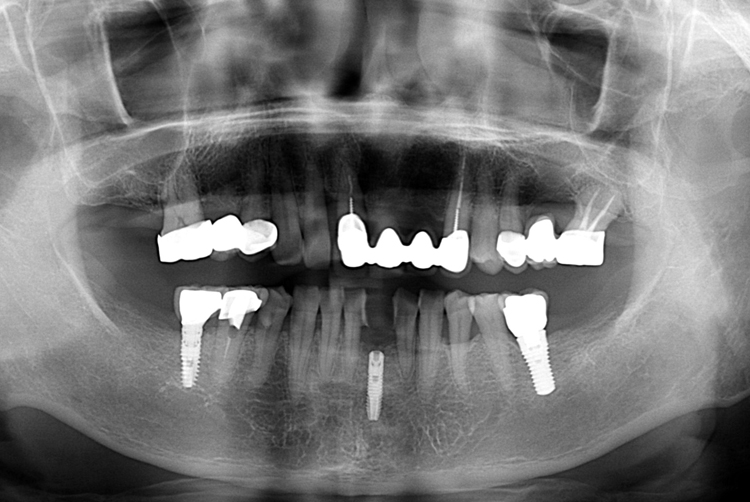

[임플란트] 어금니 임플란트

치료후 : 2018-06-22

세종치과는 많은 환자와 다양한 케이스를 바탕으로

항상 편안한 임플란트 수술을 제공하고자 노력하고,

오래동안 튼튼히 쓸 수 있는 임플란트 수술을 가장 큰 목표로 삼고 있습니다.